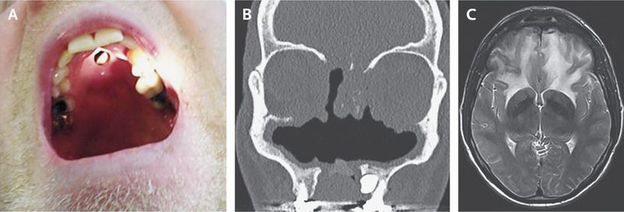

A 44-year-old man with a history of cocaine use presented with a 1-year history of headache and progressive frontal-lobe syndrome. Physical examination revealed ophthalmoparesis that was due to mechanical restriction of eye movements, mild unilateral (right) pyramidal tract signs, and a defect in the palate (Panel A). Computed tomography revealed extensive destruction of the osteocartilaginous structures of the nasal cavity (Panel B). Magnetic resonance imaging revealed extensive edema of the frontal lobes (Panel C shows a T2-weighted Laboratory testing revealed a positive serum test for antineutrophil cytoplasmic antibody (ANCA) and normal cerebrospinal fluid. Bacterial and fungal cultures of tissue were negative. Histopathological examination revealed chronic inflammation, which can be seen in the case of cocaine use or granulomatosis with polyangiitis. However, no pathognomic lesions that were suggestive of granulomatosis with polyangiitis were seen. Cocaine-induced midline destructive lesions may be the result of a necrotizing inflammatory tissue response that is triggered by cocaine use. Differentiation between cocaine-induced lesions and granulomatosis with polyangiitis can be difficult. Positive test results for ANCA may be found in patients with cocaine-induced lesions, with the result that these lesions may be confused with granulomatosis with polyangiitis, although ANCA testing in the case of inflammation due to cocaine use is often directed against human neutrophil elastase. Treatment includes abstention from cocaine use, débridement, and treatment of any bacterial superinfection. There is no role for immunosuppressive therapy. This patient stopped using cocaine and is doing better, although he still has a mild frontal-lobe syndrome.